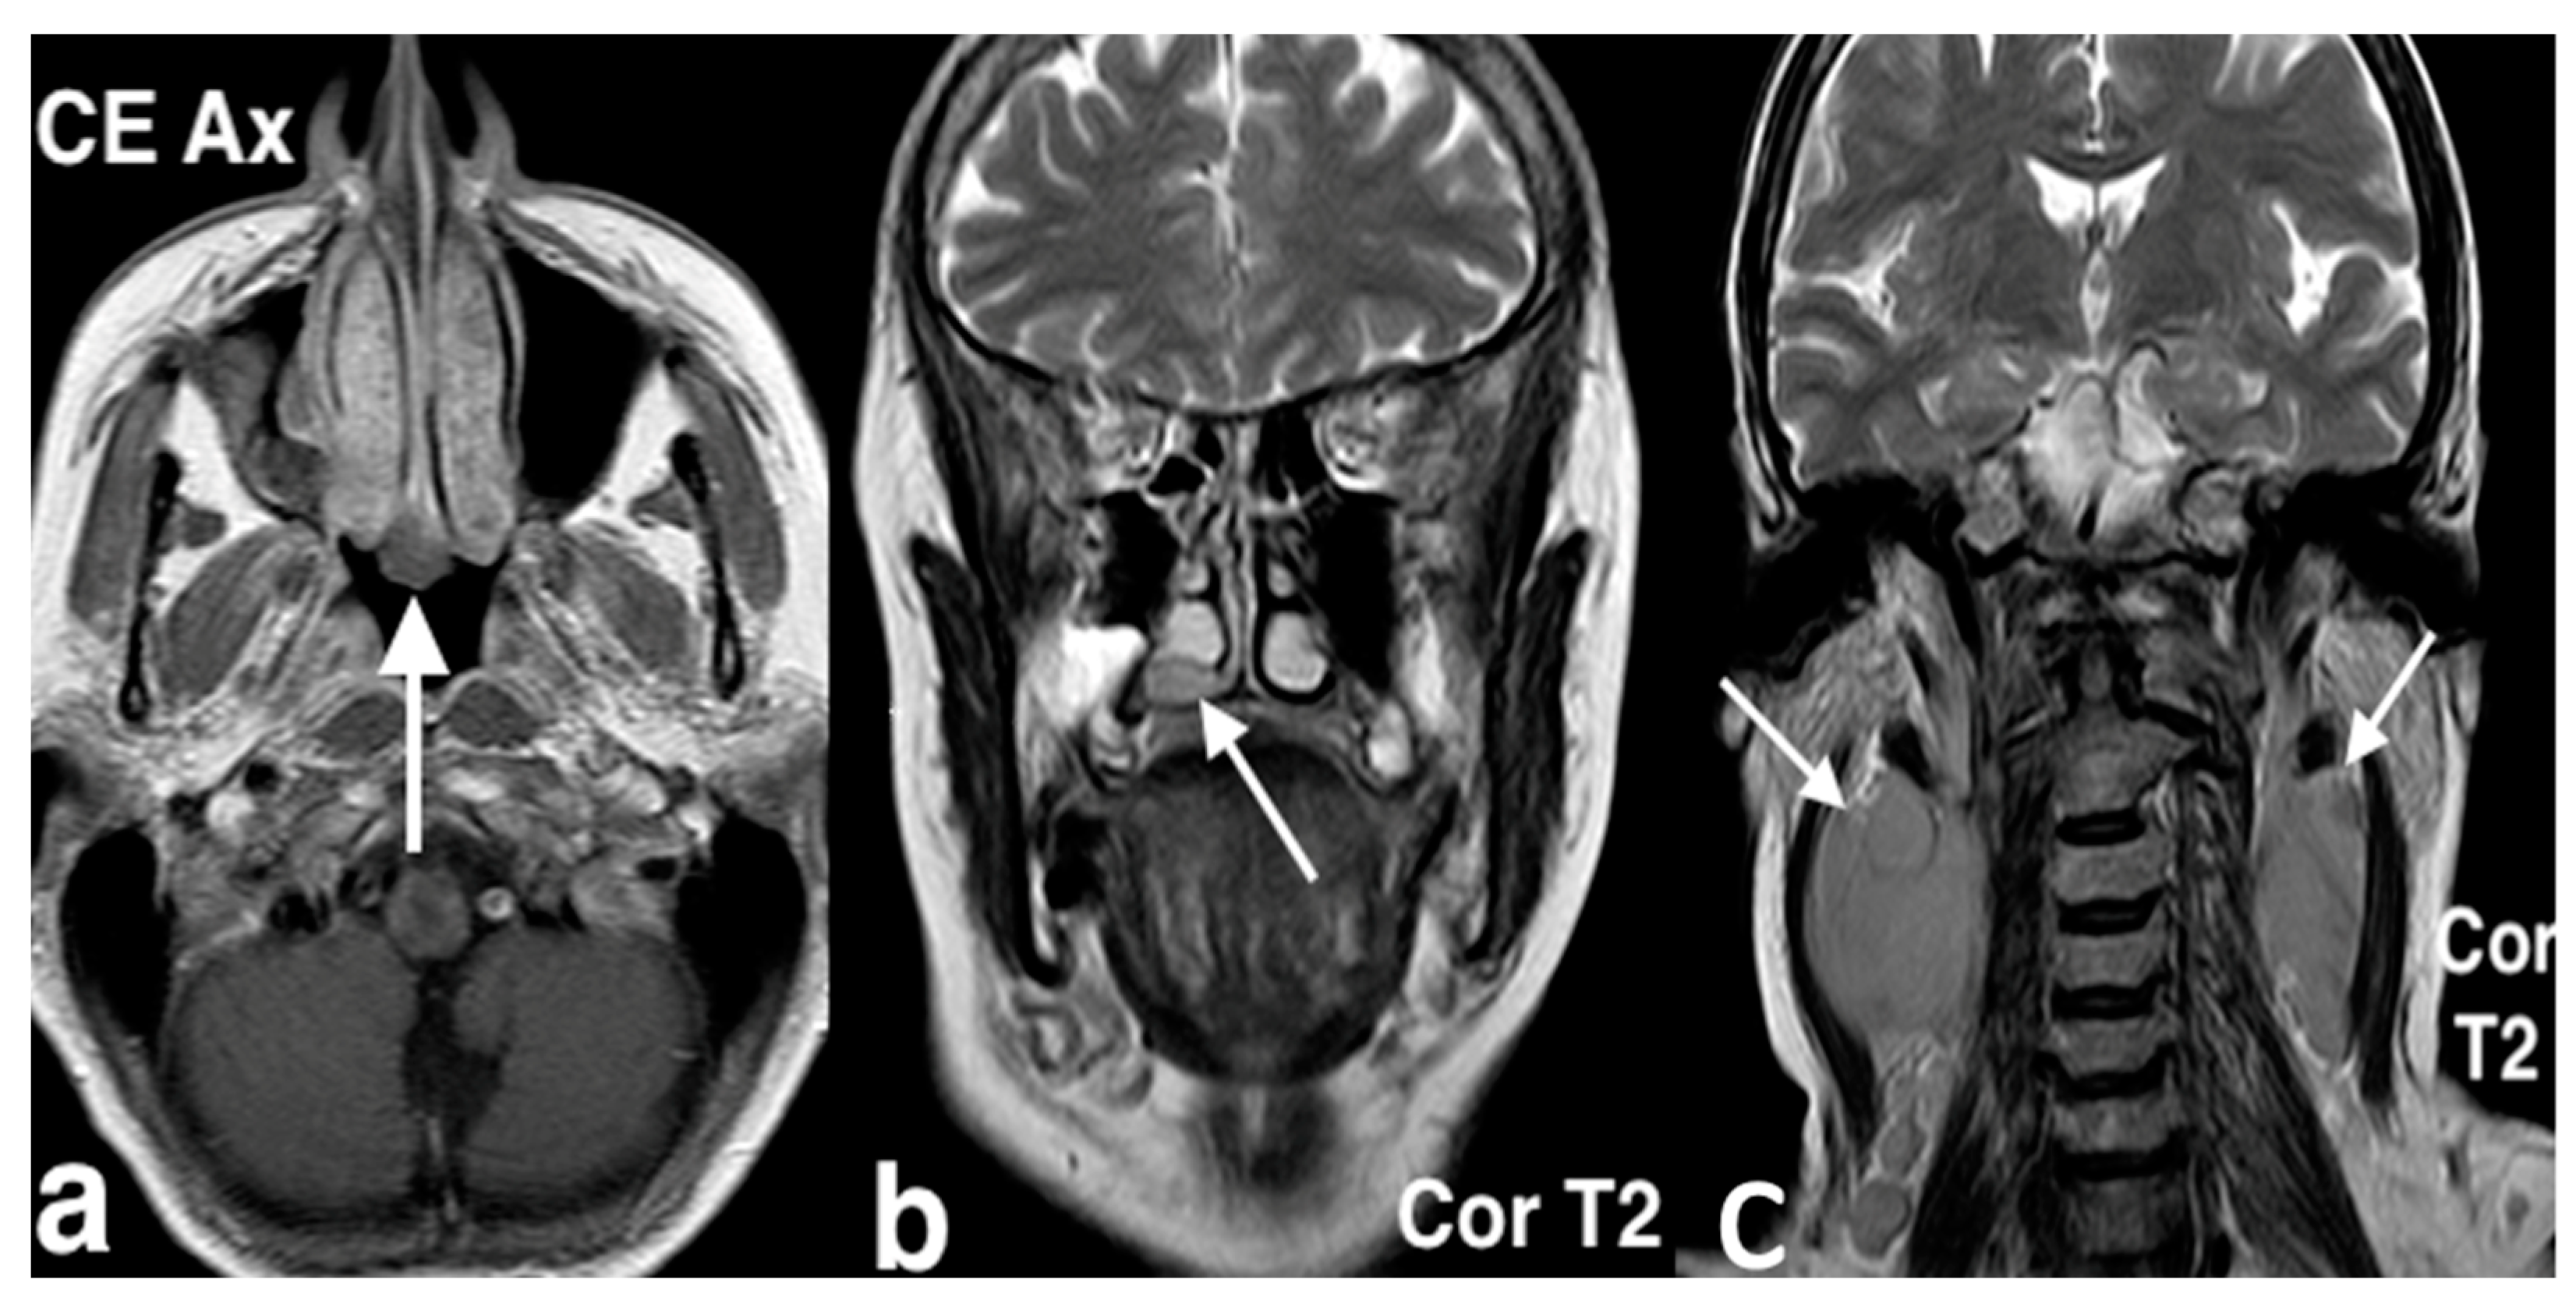

3.3.2. Esthesioneuroblastoma